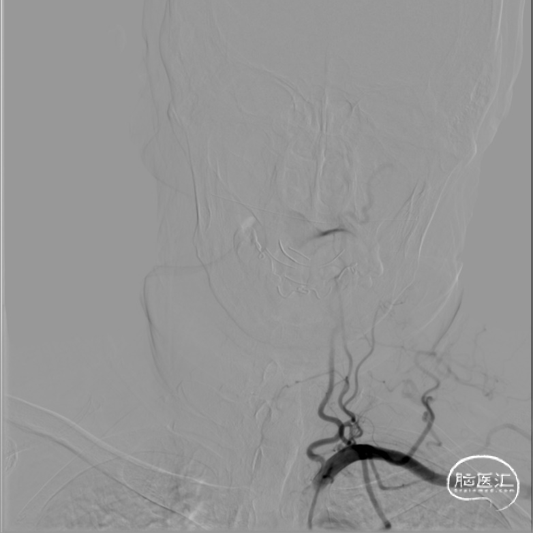

右侧桡动脉穿刺置动脉鞘,泥鳅导丝配合6F 115cm Valent®颅内支撑导管内嵌行至右侧锁骨下动脉近右侧椎动脉起始段处,将导丝配合中间导管上行至椎动脉V3段,撤出泥鳅导丝,手推造影,显示:基底动脉中段可见重度狭窄,狭窄率约80%。

将微导丝头端置右侧大脑后动脉,沿微导丝引入2.0*10mm球囊,小心扩张狭窄段,撤出球囊后造影,原有狭窄较前稍好转,沿微导丝引入支架用微导管置于基底动脉,撤出微导丝,保留微导管,沿微导管引入3.5*15mm Neuroform EZ支架,缓慢释放,复查造影,狭窄较前明显好转,支架贴壁良好。